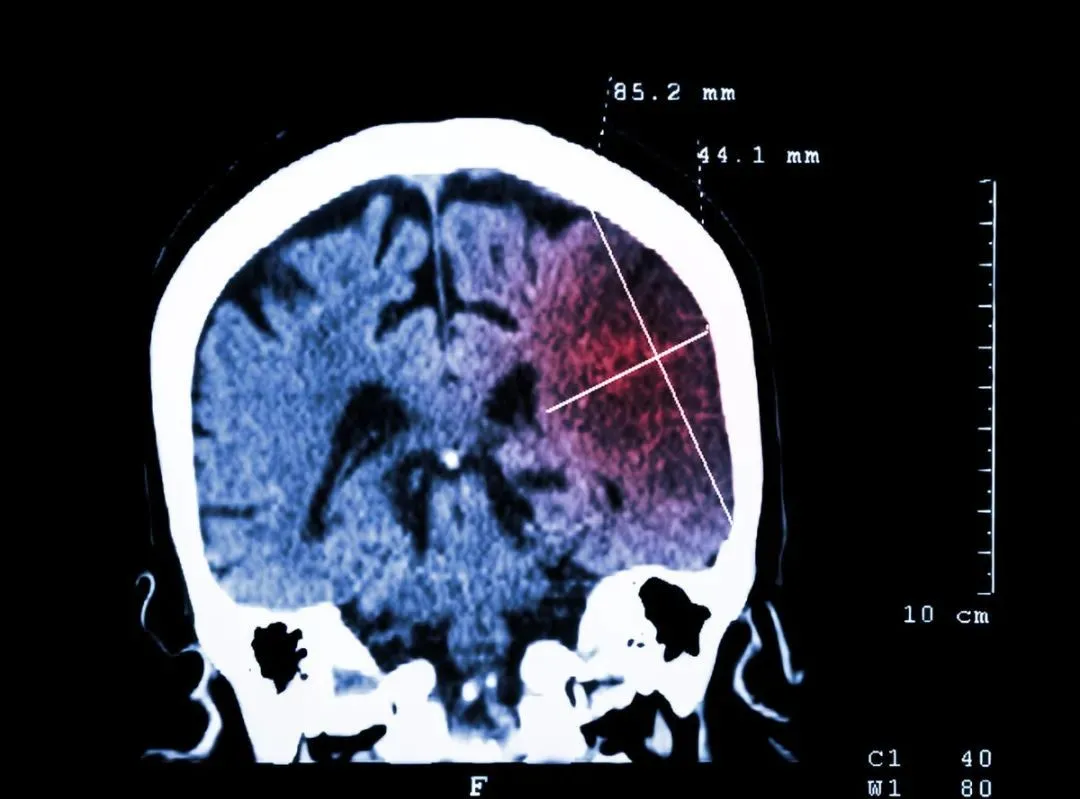

今年60岁的李老太前些日子因为突然头痛去就医,通过检查医生发现她的头部有大面积脑梗和脑疝生成。

导致这一起悲剧的根源,就是李老太本身就有高血压,在打麻将时因为情绪激动导致血压短时间内快速升高,并出现了血栓脱落,从而引起的脑梗。